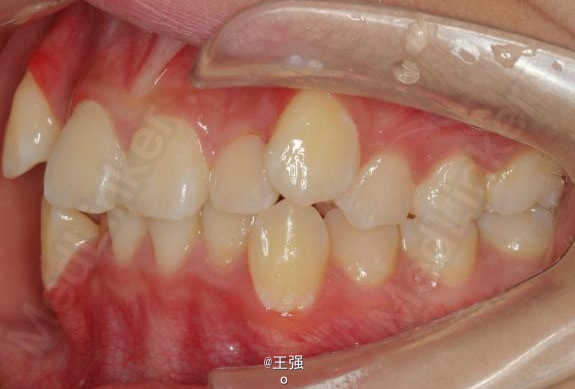

在临床上,我们常常会遇到亚类病例,对于亚类病例,有时需要不对称拔牙,常见的不对称拔牙方法有:上颌对称,下颌数目对称但是位置不对称。还有上颌对称,但是下颌数目不对称。其目的就是为了取得尽可能理想的尖窝对应咬合关系 该病例右侧是中性关系,左侧是中性偏远中关系,上颌中线正,下颌中线左偏约1mm。左侧磨牙关系距离中性关系约差2mm左右。如果采用对称性拔除下颌左右四,我们面临的问题是,一、如何保证矫治后上下中线一致,二、如何保证左侧磨牙关系矫治后为中性关系。治疗过程中势必会用到不对称牵引。我个人认为除非是功能性的因素,矫治过程中最好不要用不对称牵引。 关于中线和磨牙关系的问题,我认为应在矫治计划制定时就应考虑到,而不是等到矫治第三阶段所谓精细调整阶段再来解决。事实上到了这个阶段采用了不对称的牵引,即使暂时取得了中线对齐的矫治目的也是不稳定的。 这个病例,用了不对称的拔牙,右下拔四,左下拔五。下颌牙齿在漂移的过程中(几乎没有外来力量),下前牙自然就会向右比向左多漂移一些,中线在下颌还没有开始矫治时就对齐了,左下六因没有五的存在,自然就向近中多漂移一些,和上颌六形成中性关系。接下来的矫治就会非常简单,而结果自然也非常稳定。